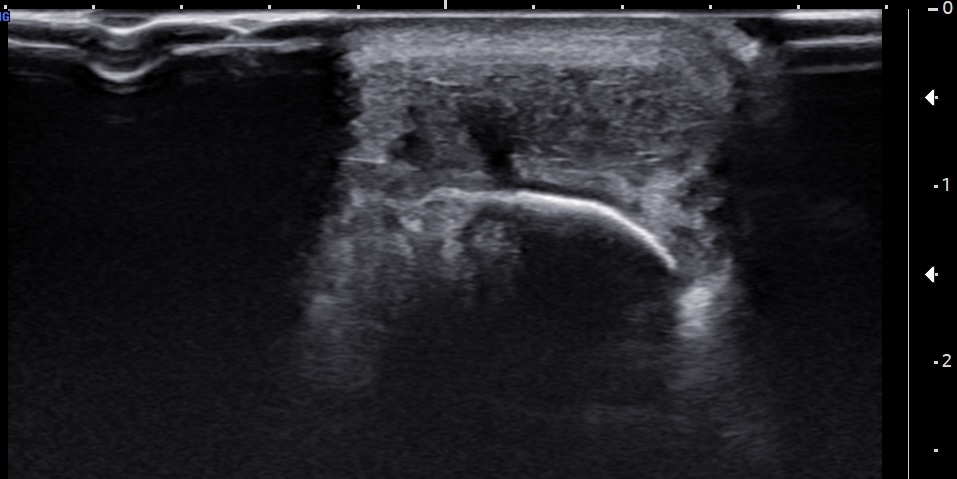

Labeled short-axis ultrasound image of the insertional Achilles tendon, a few millimeters distal to the superior edge of the calcaneus, demonstrating findings similar to those in Figure 4, with the addition of a clearly visible subcortical cyst.

Labels: AT: Achilles tendon, C: calcaneus, solid arrow: subcortical cyst, dashed arrow: partial tear.